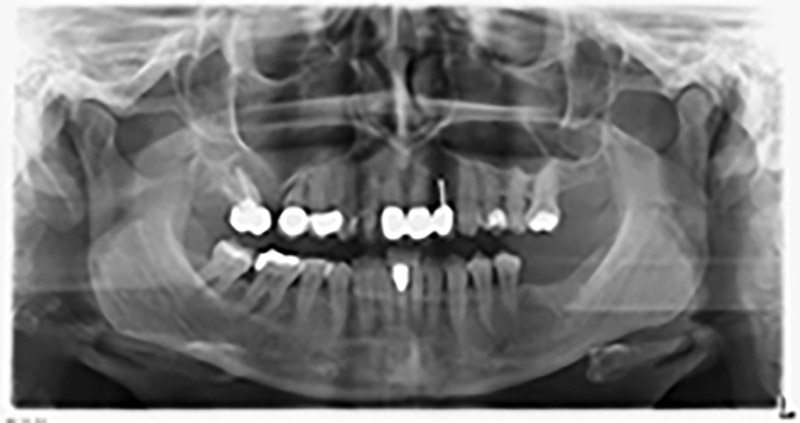

Per ridurre l'accrescimento nella regione 14, con il consenso della paziente si opta per il posizionamento e l'inclinazione dell'impianto 16 in direzione dorso-craniale (fig. 8).